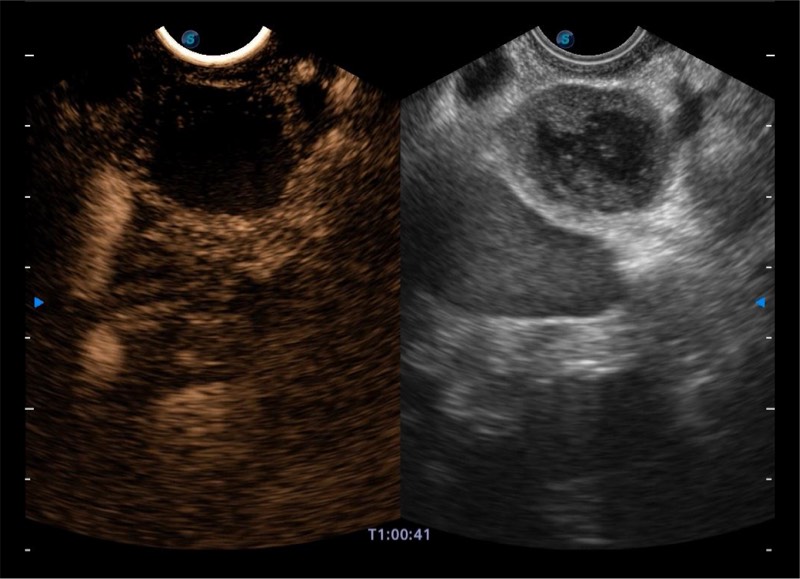

基于二十年的超声技术积累,诸侯快讯官网提供了最新一代的独立超声主机,在提供高质量图像的同时满足多学科使用。具备常见多普勒技术并提供弹性成像、声学造影等高端影像技术。新一代传感器具有更强的抗干扰能力并减少图像伪影。

4-12MHZ宽频输出